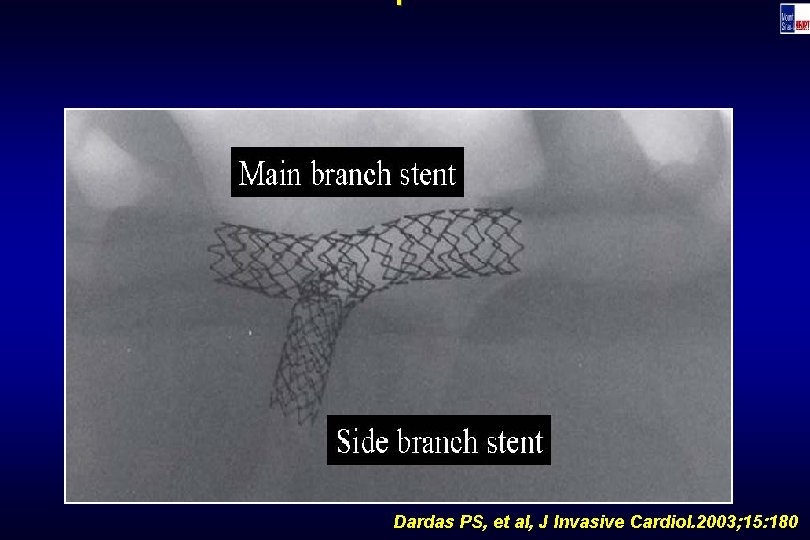

Technique Dardas PS, et al, J Invasive Cardiol. 2003; 15: 180

Technique Dardas PS, et al, J Invasive Cardiol. 2003; 15: 180

Technique Dardas PS, et al, J Invasive Cardiol. 2003; 15: 180

Technique Dardas PS, et al, J Invasive Cardiol. 2003; 15: 180

Technique Dardas PS, et al, J Invasive Cardiol. 2003; 15: 180

Technique Dardas PS, et al, J Invasive Cardiol. 2003; 15: 180